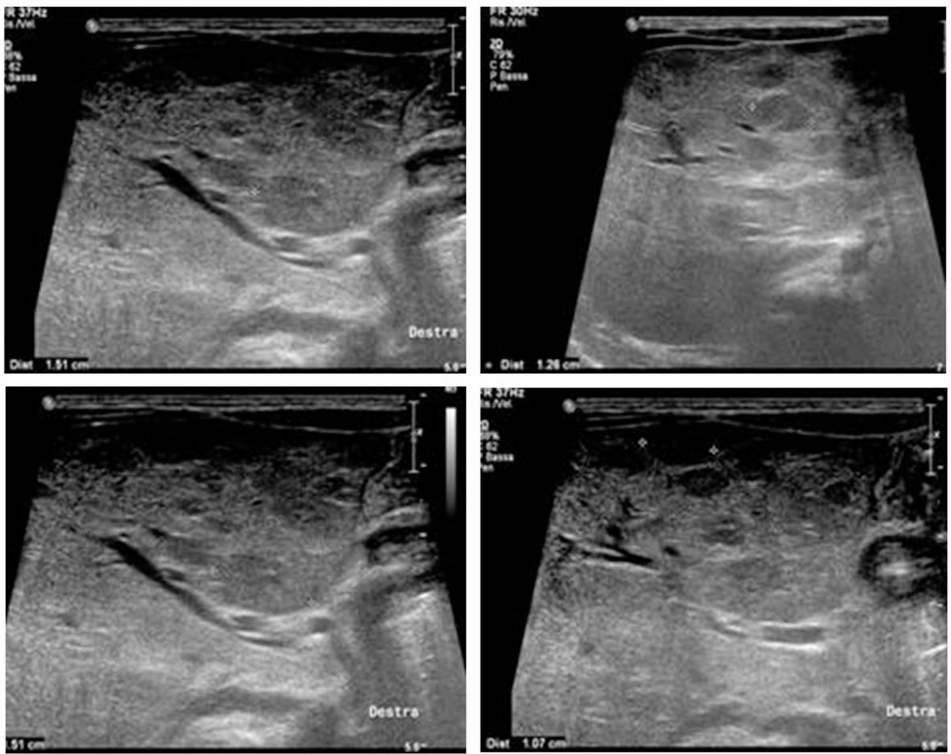

病例显示,普萘洛尔治疗后14天TSH从33.05降至5 microU/mL,30天后肝结节直径从20mm显著缩小。影像学显示治疗前肝脏几乎完全被肿瘤取代: